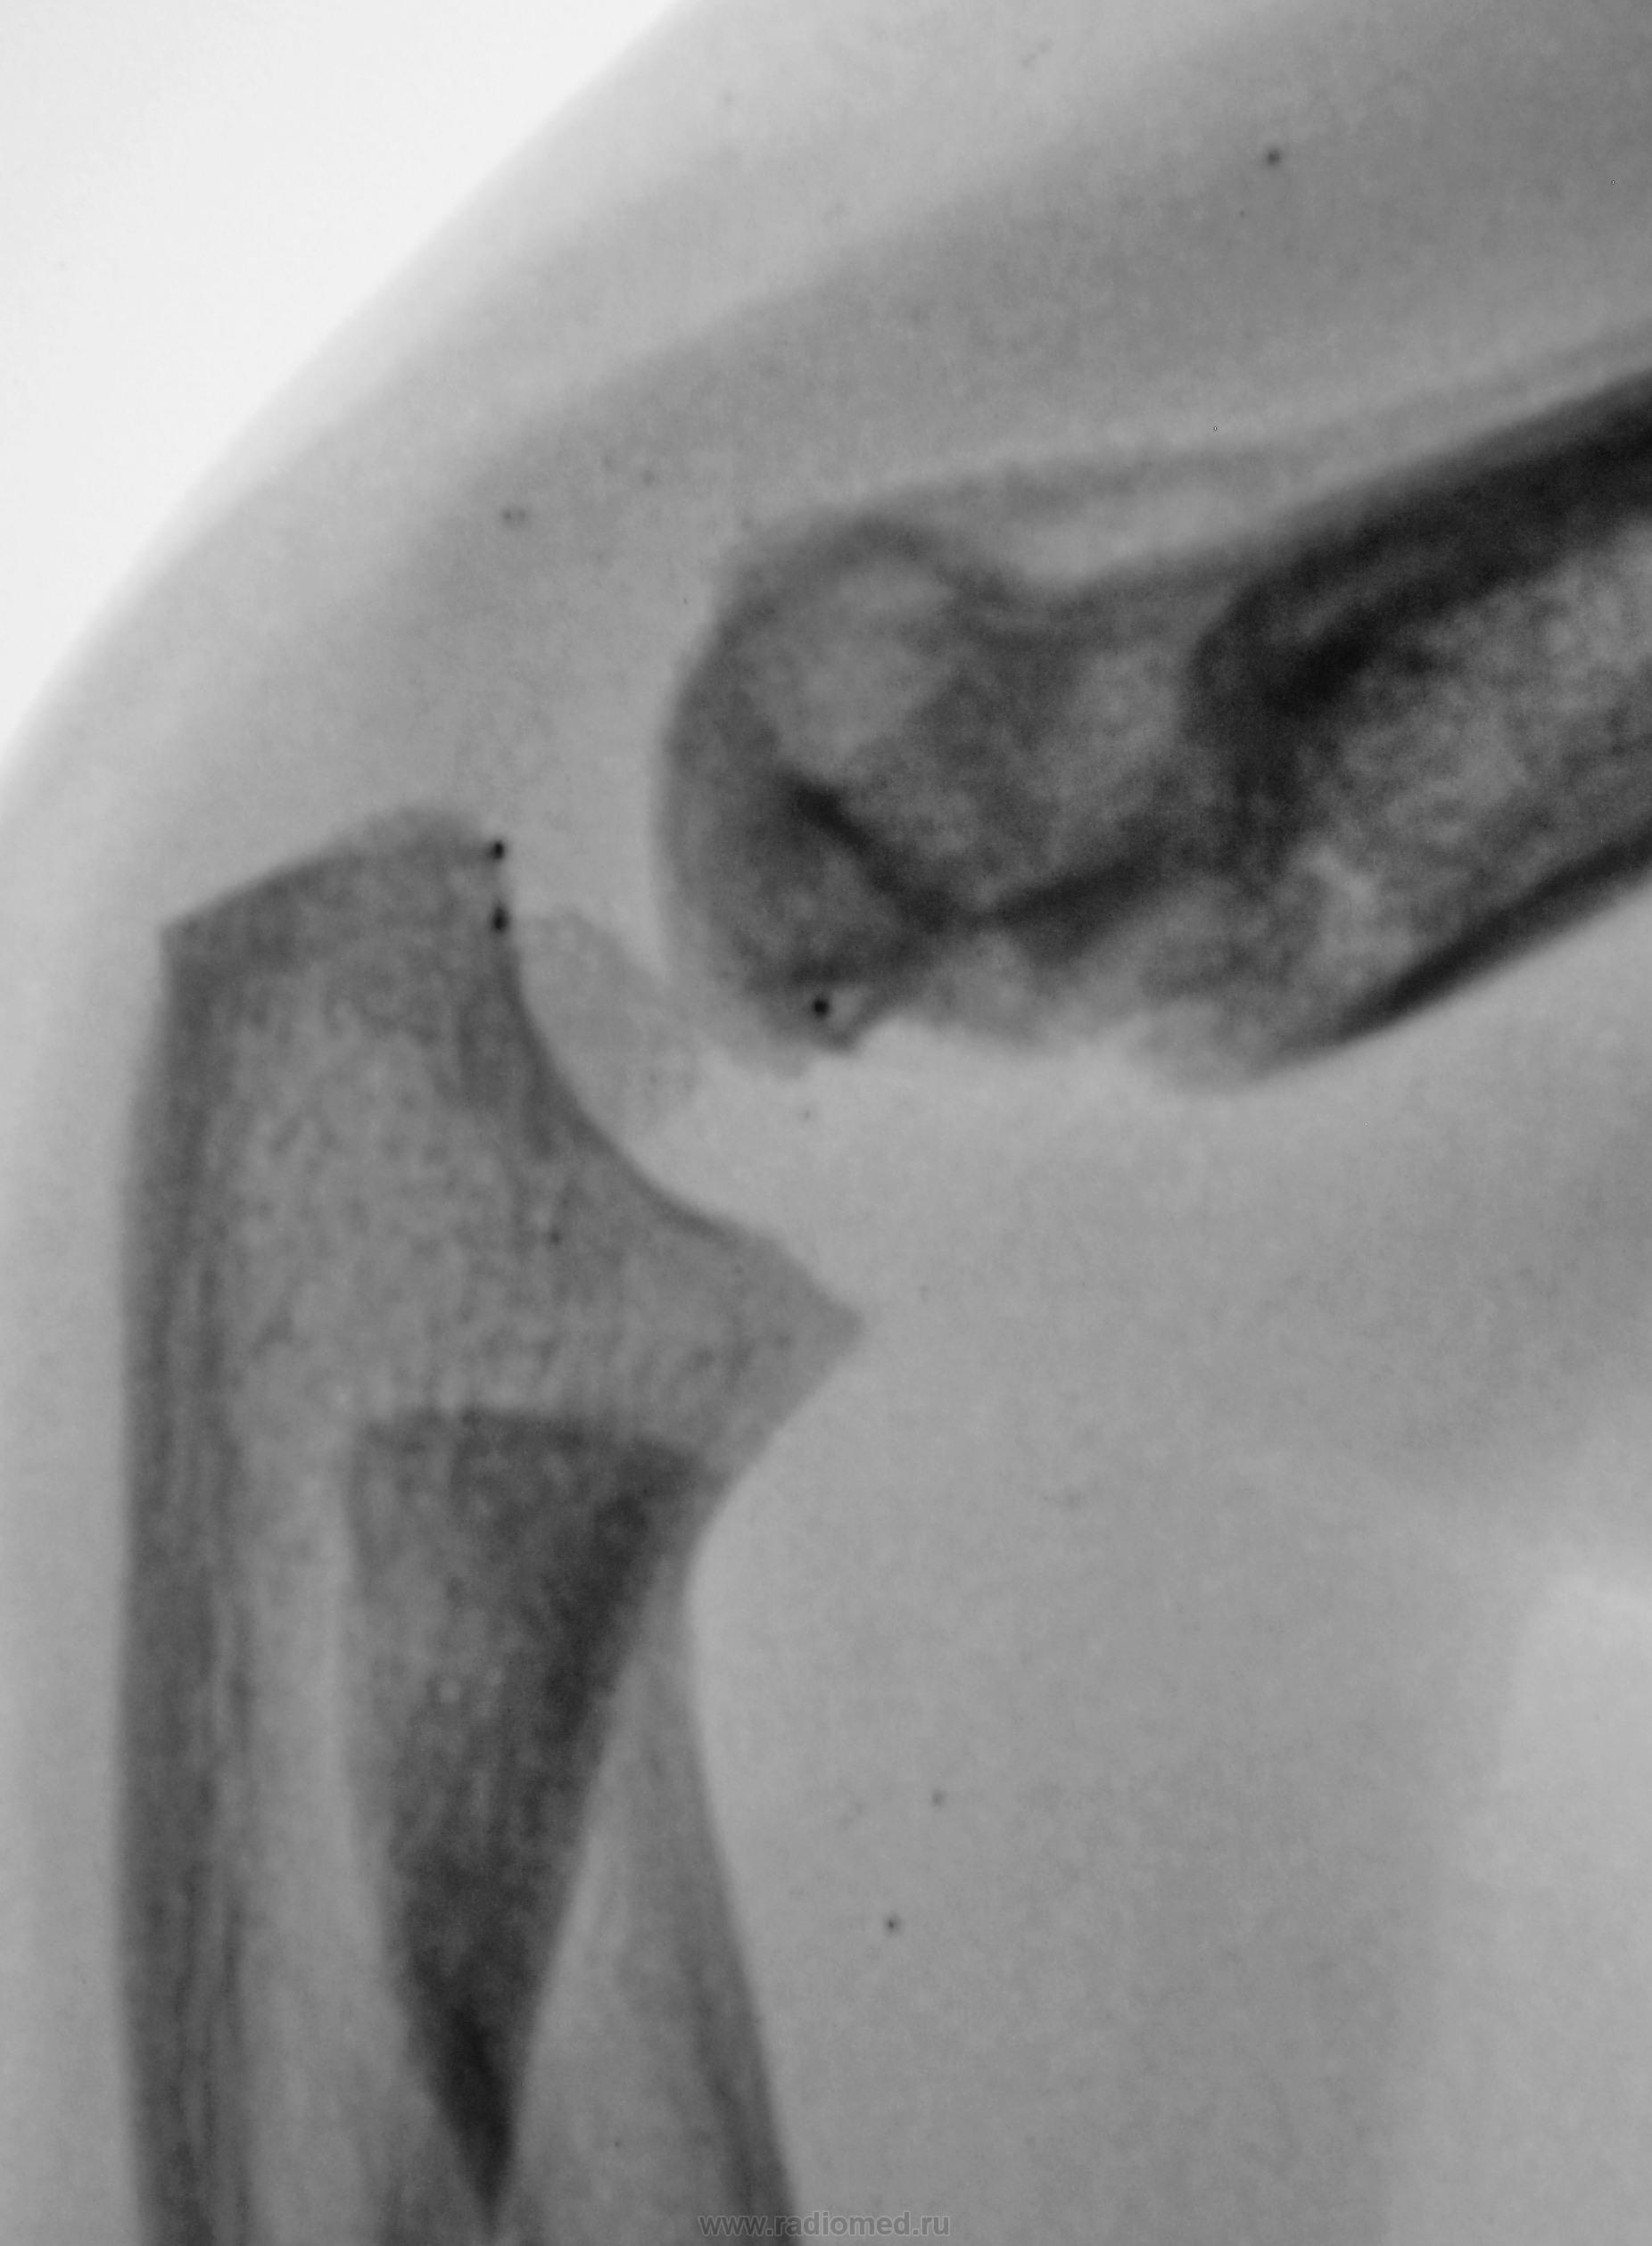

Ребенок. Снят гипс.

Первичный снимок.

3 года.

Консолидирующийся чрезмыщелковый перелом плечевой кости. Есть, конечно, угловое смещение кзади, надо было сразу репонировать, а теперь не знаю, может, для такого возраста можно и оставить.

углок есть, консолидация достаточная для того, чтобы уже начать разрабатывать сустав. Все не так уж и плохо))))

Обычный срастающийся с допустимым смещением чрезмыщелковый перелом. Подвывихов нет.